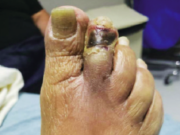

Exploring the effectiveness of Topical Wound Oxygen therapy in diabetic foot and venous leg...

This advertorial is sponsored by AOTI.

Until about a decade and a half ago, vascular surgeon Alisha Oropallo, MD, could be counted among the skeptics....

Cyclical-pressure Topical Wound Oxygen therapy emerges as a proven wound-healing device for diabetic foot...

Enrico Ascher, MD, and Natalie Marks, MD, currently combine for close to 60 years of vascular surgery practice experience...

Cyclical topical wound oxygen therapy: A new generation of wound healing device showing sustained...

In the beginning, it took a little convincing for Anil Hingorani, MD, to come around to the idea that...